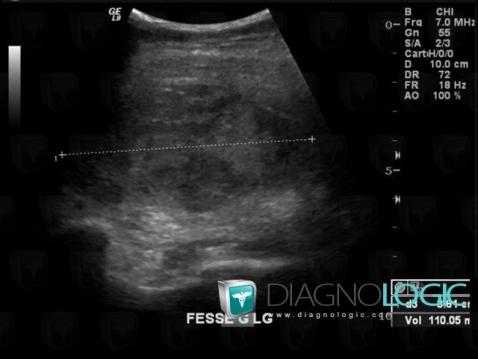

Hematoma, Pelvic Muscles, Other soft tissues/nerves - Pelvis, US

Here is the specific information in the key image above:

- Diagnosis Hematoma, Location(s) Other soft tissues/nerves - Pelvis, with gamuts Pelvic Muscles, with gamuts